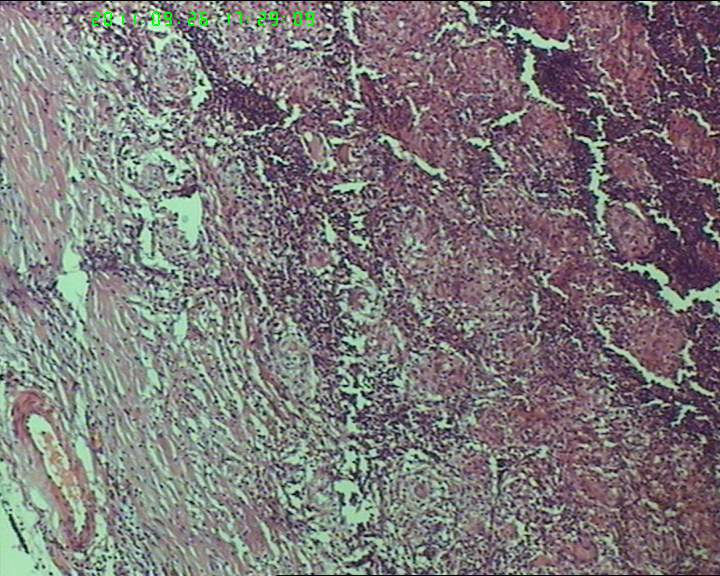

21岁女性左侧颌下淋巴结,该诊断什么?

灰白不整形肿物一个,大小3.5*2.5*2cm,包膜完整。

21岁女性左侧颌下淋巴结,该诊断什么?图3

慢性肉芽肿性炎症,形态学倾向结节病,但是作为病理工作者对于这样的病例,再结合咋们国情,还是建议临床除外增殖性结核后再考虑结节病。

肉芽肿性炎症,倾向结节病。

肉芽肿性炎,考虑结核不除外结节病